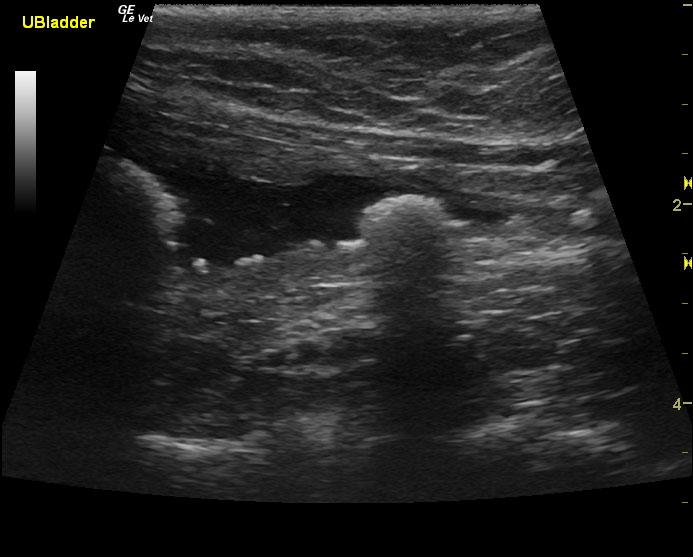

A 7-year-old FS DSH was presented for evaluation of recurrent hematuria and stranguria. Urinalysis showed protein and blood and a normal specific gravity. Culture was negative.

A 7-year-old FS DSH was presented for evaluation of recurrent hematuria and stranguria. Urinalysis showed protein and blood and a normal specific gravity. Culture was negative.